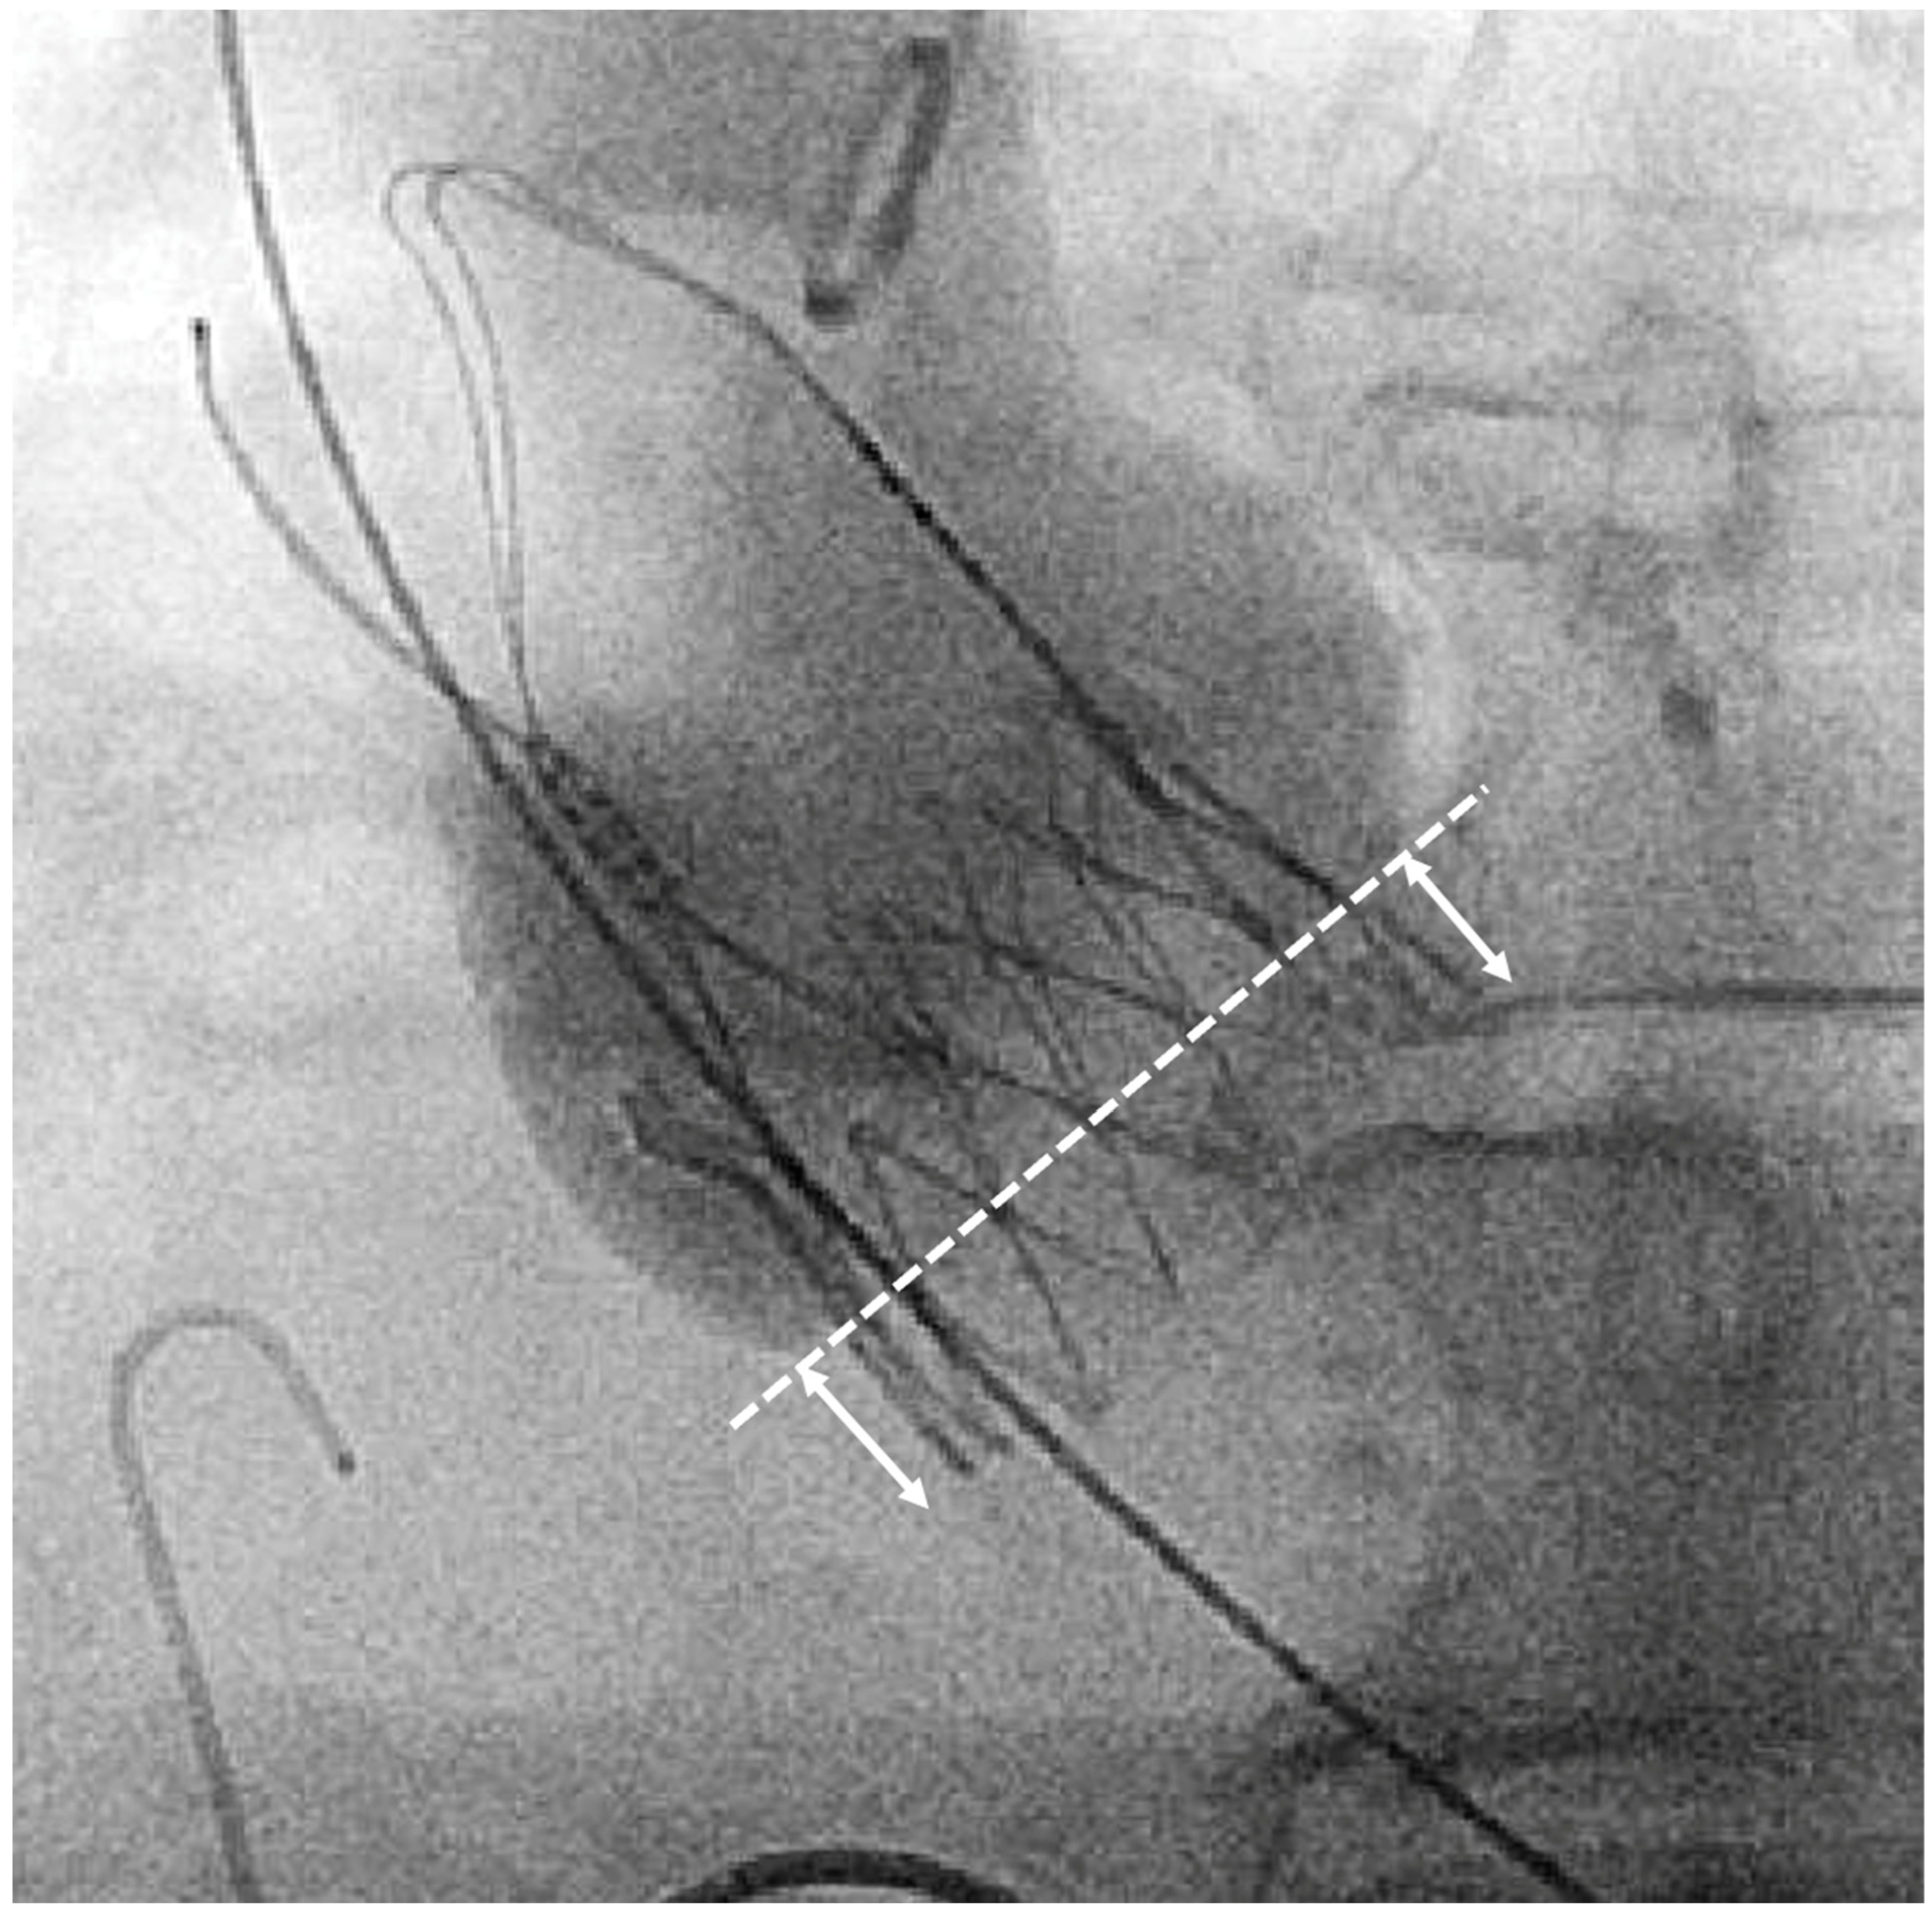

The manufacturer recommends a landing zone corridor for SE NEO2. All prostheses were initially intended to be implanted in the recommended landing zone. Assessment of the ID was performed retrospectively in the cusp-overlap view (Figure 1). We rated the implantation based on the measured ID < 3 mm as high, between 3 and 7 mm as recommended, and >7 mm as low (Figure 2).

Figure 1.

Fluoroscopic measurement of implantation depth at non-coronary-cusp (NCC) in the cusp-overlap view. Arrows indicate implantation depth (ID).